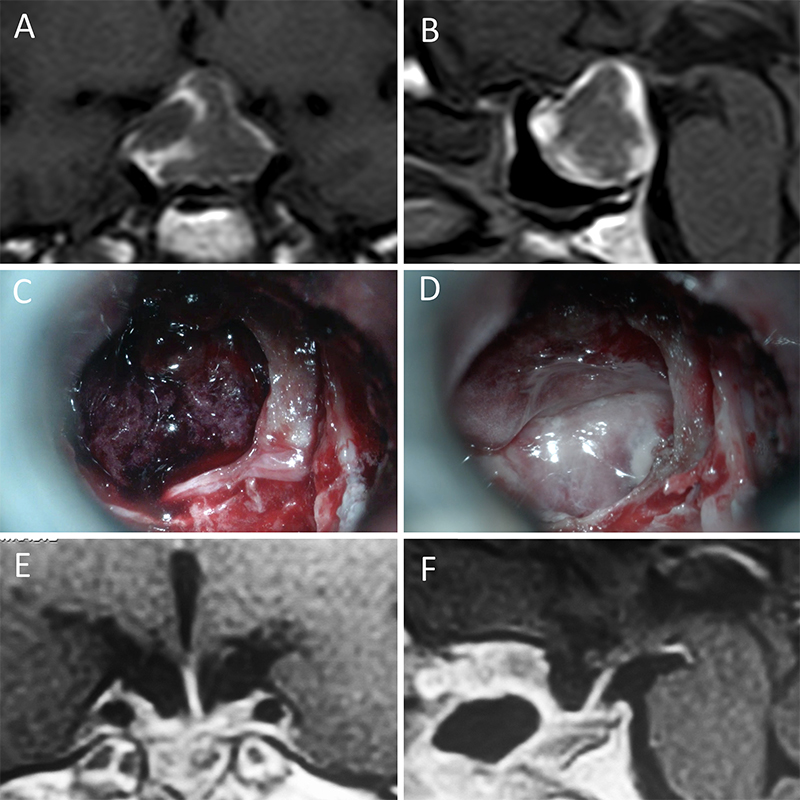

Figura 3: Macroadenoma no funcionante en un hombre de 64 años. El paciente presentó en el preoperatorio déficit visual que mejoró tras la cirugía. A-B: RM preoperatoria; C-D: intraoperatorio; E-F: RM postoperatoria.